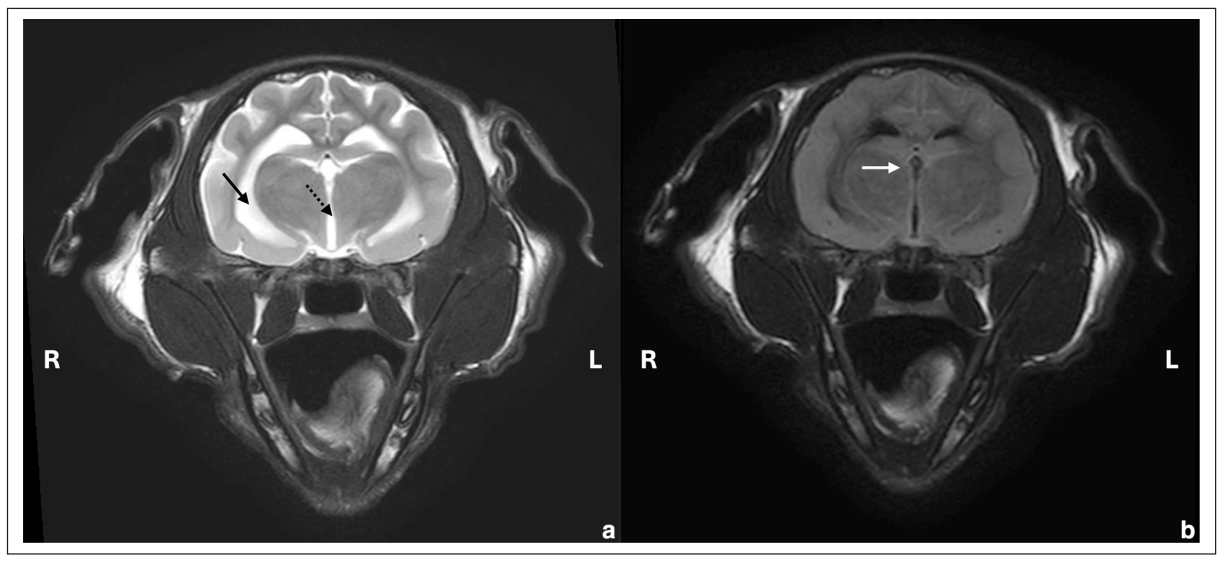

第66天,进行了高场强脑部和颈椎MRI检查。发现延髓至C5的髓内病变、脊髓肿胀(图1)、中度脑室扩大(图2)以及多灶性脑膜增厚且对比增强显著(图3)。肿胀限制了对枕大池的通路,因此需要进行腰椎穿刺而不是寰枕部穿刺以获取脑脊液。

↑ 图2. 大脑丘脑和第三脑室水平的横断面图像,(a) T2W和(b) T2 FLAIR图像。脑室系统中度增宽(箭头:侧脑室,虚箭头:第三脑室),FLAIR序列中脑脊液抑制不完全(白箭头)。